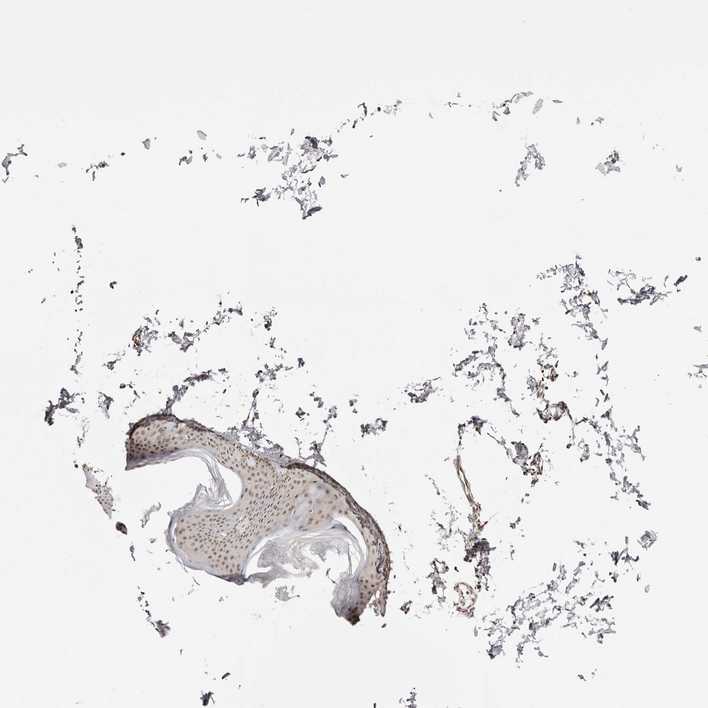

SKIN 1 - Antibody stainingi

Antibody staining in the annotated cell types in the current human tissue is reported as not detected, low, medium, or high, based on conventional immunohistochemistry profiling in selected tissues. This score is based on the combination of the staining intensity and fraction of stained cells.

Each image is clickable and will lead to virtual microscopy that enables deeper exploration of all samples and also displays staining intensity scores, fraction scores and subcellular localization as well as patient and tissue information for each sample.

Antibody HPA027907

Langerhans Low

Fibroblasts Medium

Keratinocytes Medium

Melanocytes Medium

SKIN 2 - Antibody stainingi

Epidermal cells Medium